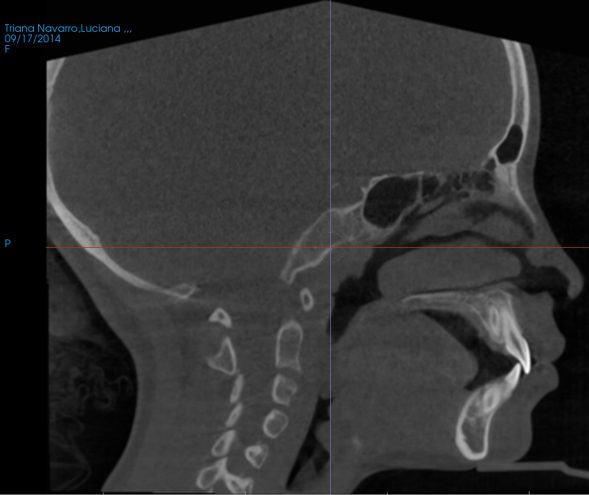

- Relación con postura y crecimiento

- Posición mandibular

- Colapso posterior de lengua

- Relación con columna cervical

Aquí conectas perfecto con:

- SNA

- postura

- desarrollo craneofacial

- Predicción de riesgo respiratorio

- Áreas críticas estrechas

- Patrón de vía aérea colapsable